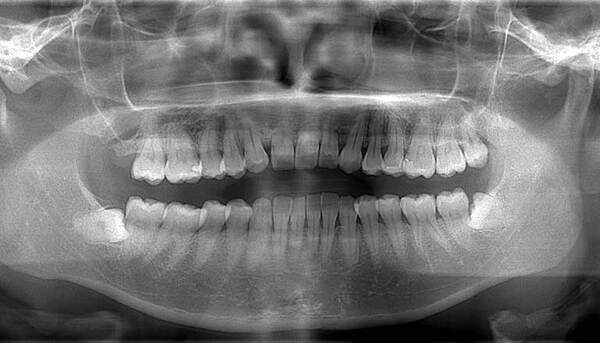

左上の親知らずですが、真っ直ぐはえています。

口腔内では大きな虫歯になっていましたので、抜歯の適応となります。